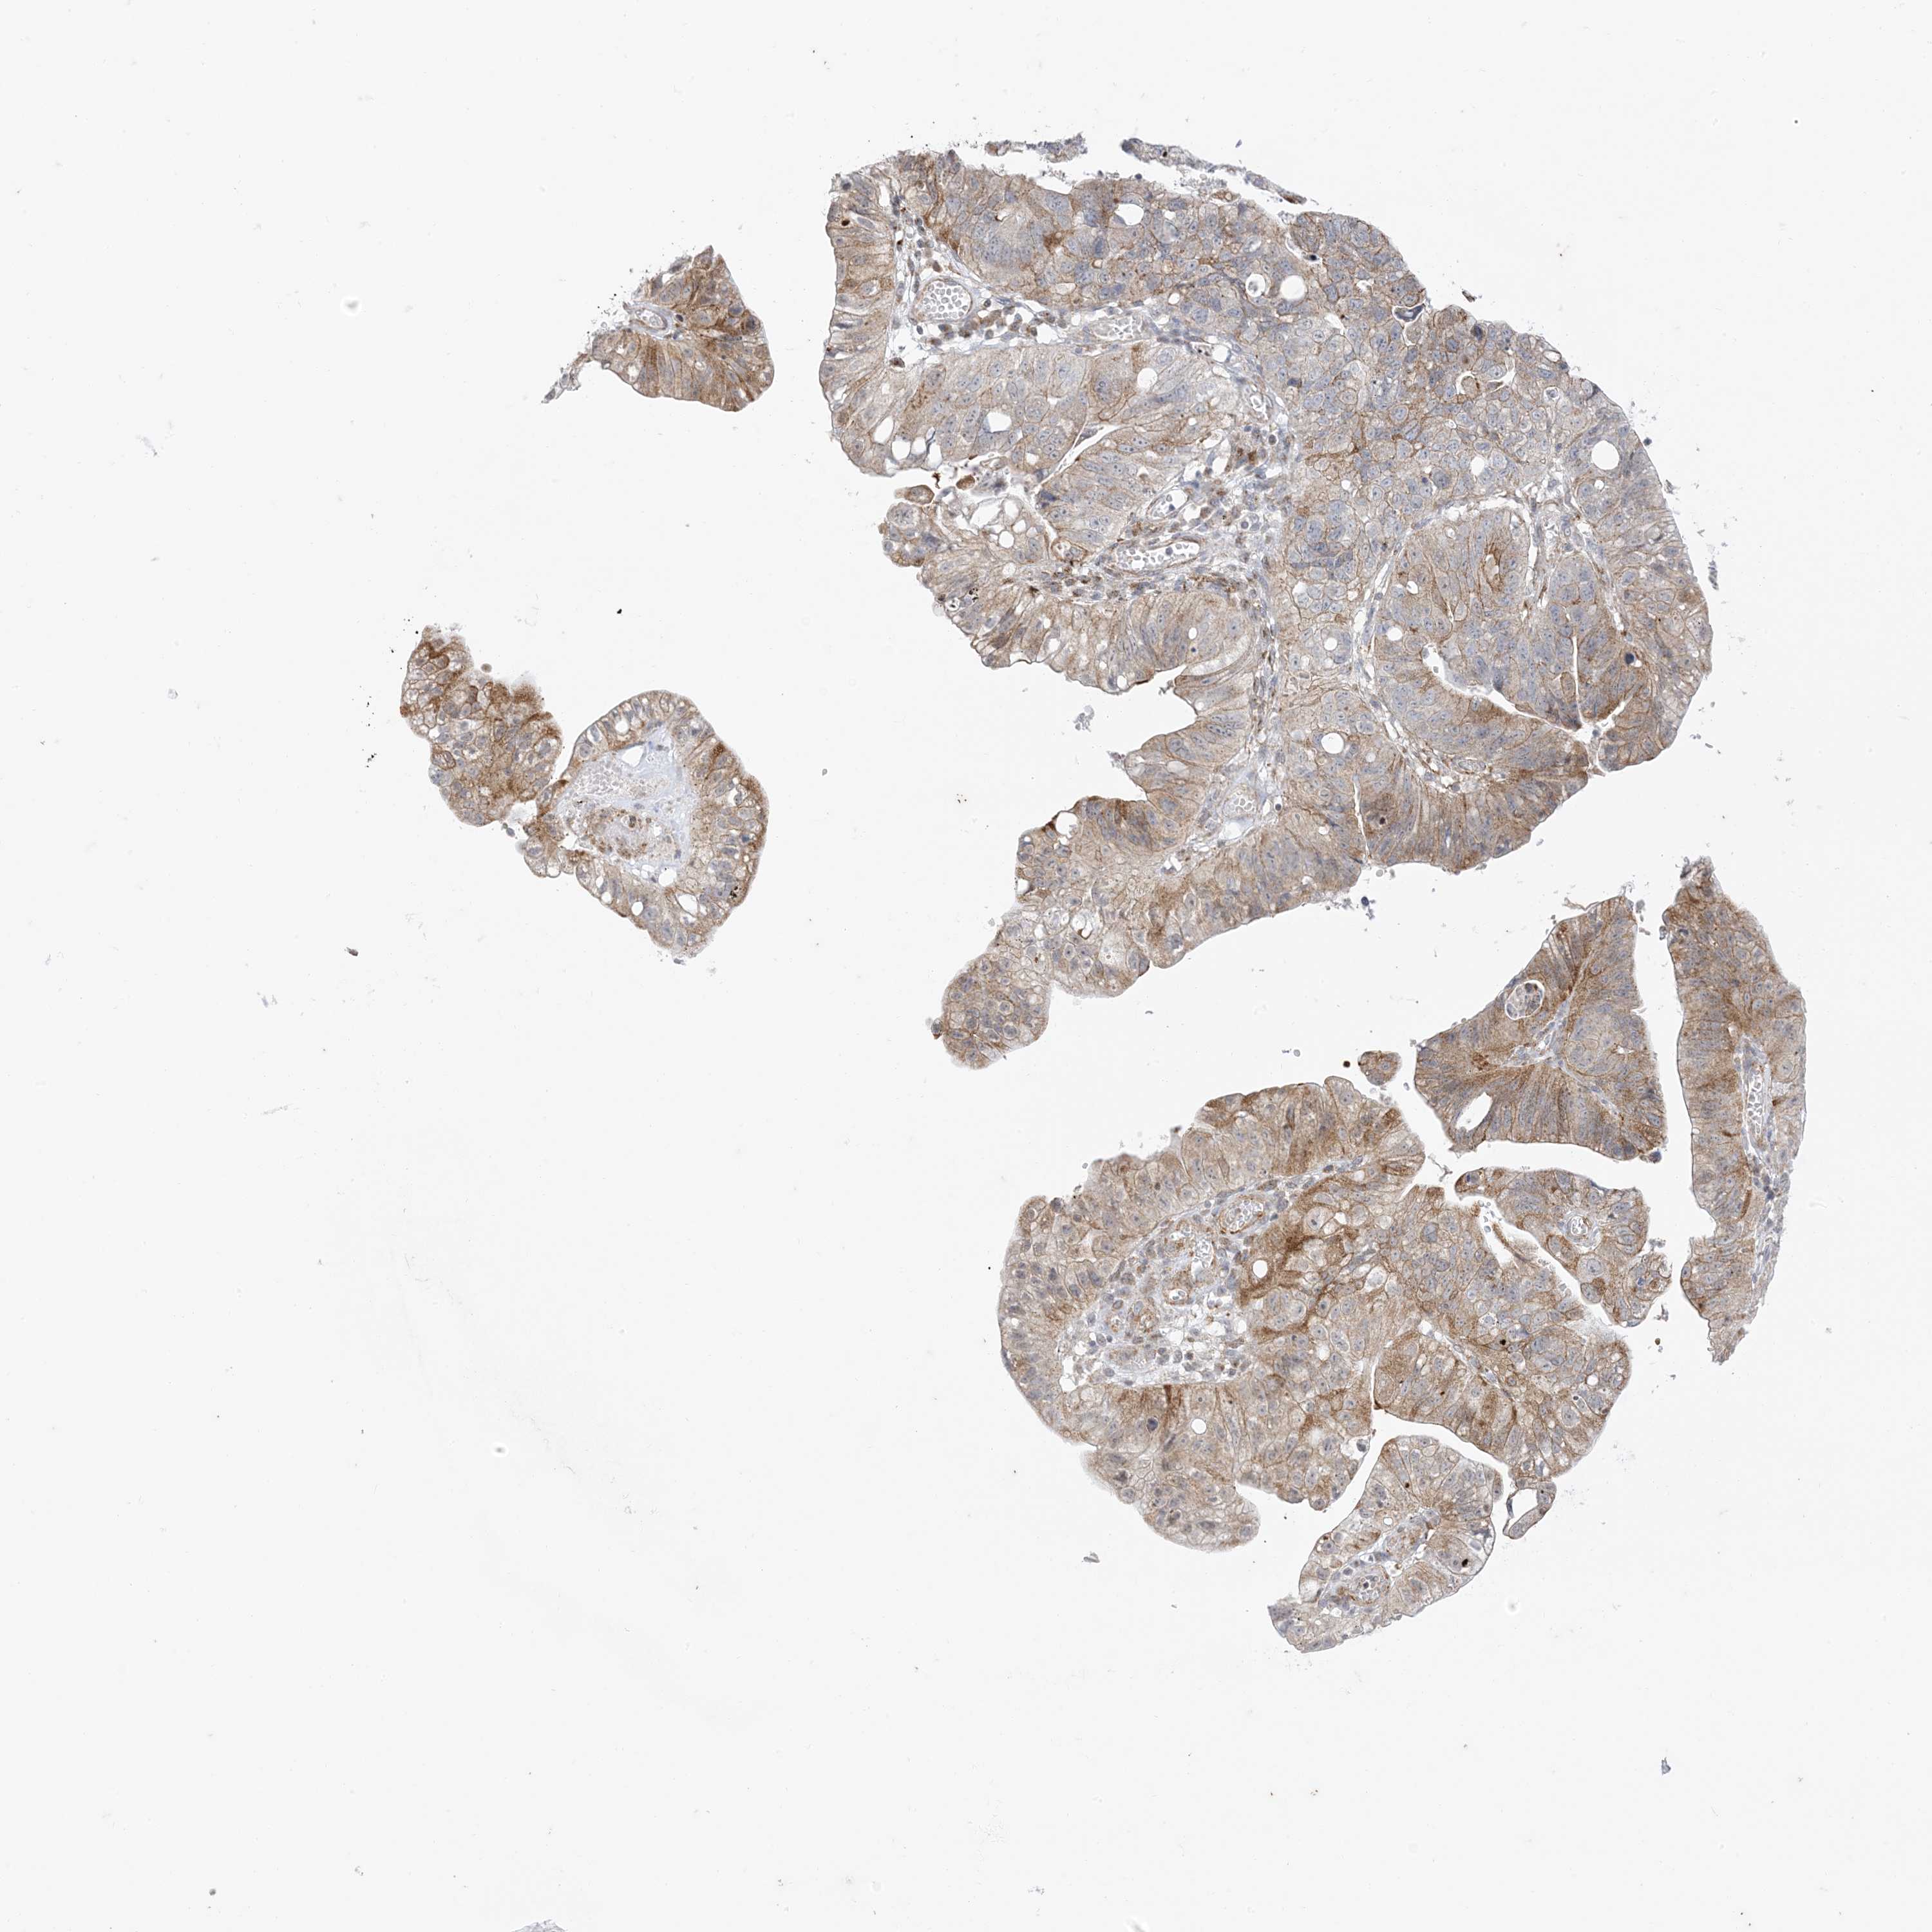

STOMACH CANCER - Protein expressioni

A mouse-over function shows sample information and annotation data. Click on an image to view it in a full screen mode. Samples can be filtered based on level of antibody staining by selecting one or several of the following categories: high, medium, low and not detected. The assay and annotation is described here.

Note that samples used for immunohistochemistry by the Human Protein Atlas do not correspond to samples in the TCGA dataset.

Antibody stainingi

Antibody staining in the annotated cell types in the current human tissue is reported as not detected, low, medium, or high, based on conventional immunohistochemistry profiling in selected tissues. This score is based on the combination of the staining intensity and fraction of stained cells.

Each image is clickable and will lead to virtual microscopy that enables deeper exploration of all samples and also displays staining intensity scores, fraction scores and subcellular localization as well as patient and tissue information for each sample.

Antibody HPA047820

Antibody CAB035994

Staining

High

Medium

Low

Not detected

Intensity

Strong

Moderate

Weak

Negative

Quantity

>75%

75%-25%

<25%

None

Location

Nuclear

Cytoplasmic/membranous

Cytoplasmic/membranous,nuclear

Adenocarcinoma, NOS